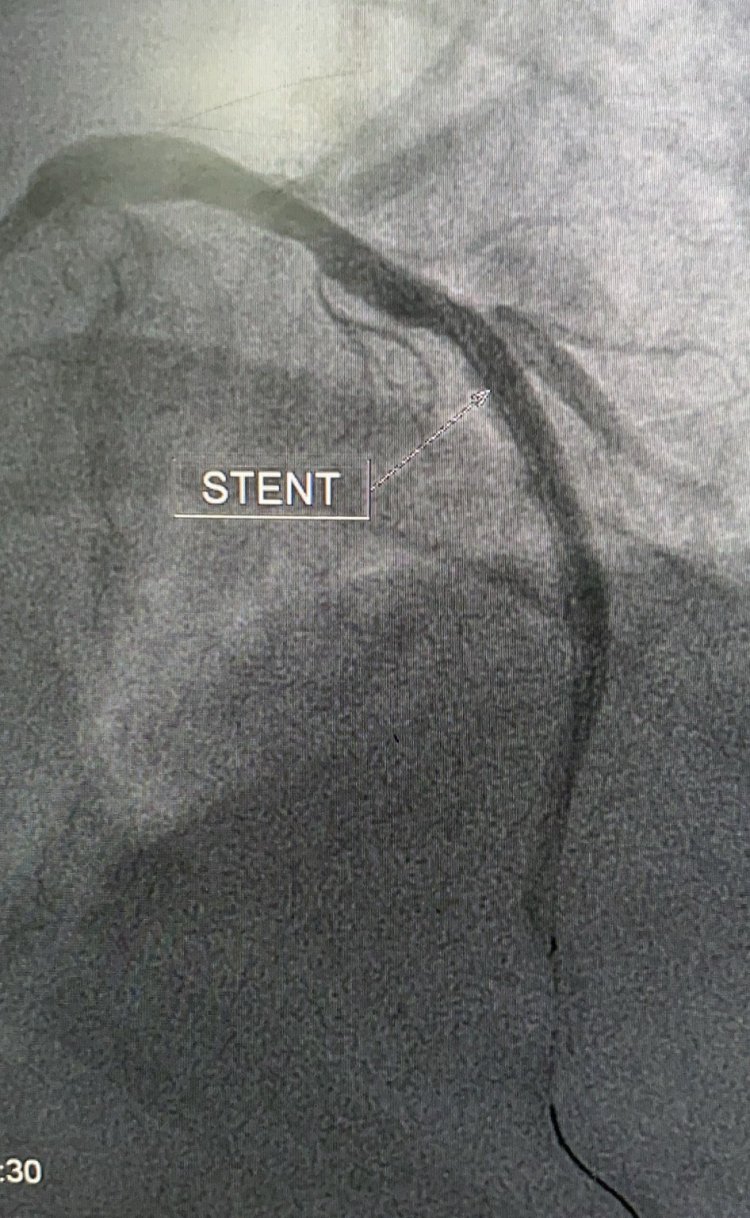

Can Thiệp Mạch Vành Cứu Sống Nhiều Người Bệnh Nhồi Máu ...

Bài viết được viết bởi Thạc sĩ bác sĩ Võ Xuân Trí, khoa Nội Tim mạch của bệnh viện.